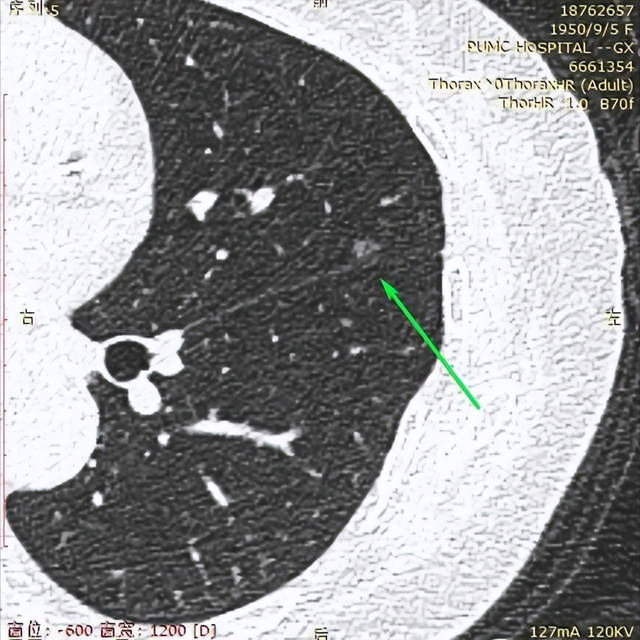

2023年11月1日我在北京也有高分辨CT的医院复查了CT。CT报告单写:双肺多发结节(省略)较大者(3im左52)长径约7mm。看主任助手帮我截图中右侧这2个结节的位置是新发吗?原右肺下叶7mm的结节我没看到。

2023年5月6日我在新桥做的CT,左肺上叶有2个1cm多大小的结节,2023年11月1日CT报告中没有描述这2个大结节,但在图像117/361和图像118/361的两张截图的上方这2个结节影还是可见。

这些情况让我很迷糊!很担忧!烦请主任帮看看我左肺在什么位置有多少个高危结节?到了什么程度?需什么时候手术?能一网打尽吗?右肺是有新发结节吗?是否有需尽快处理的结节?